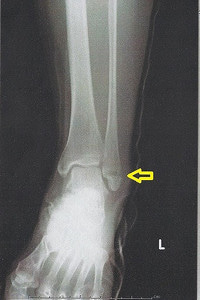

ですから、ちょっとでもおかしいなと思ったら、

病院でレントゲンを撮ってもらうのが最も早くて正確な方法です。